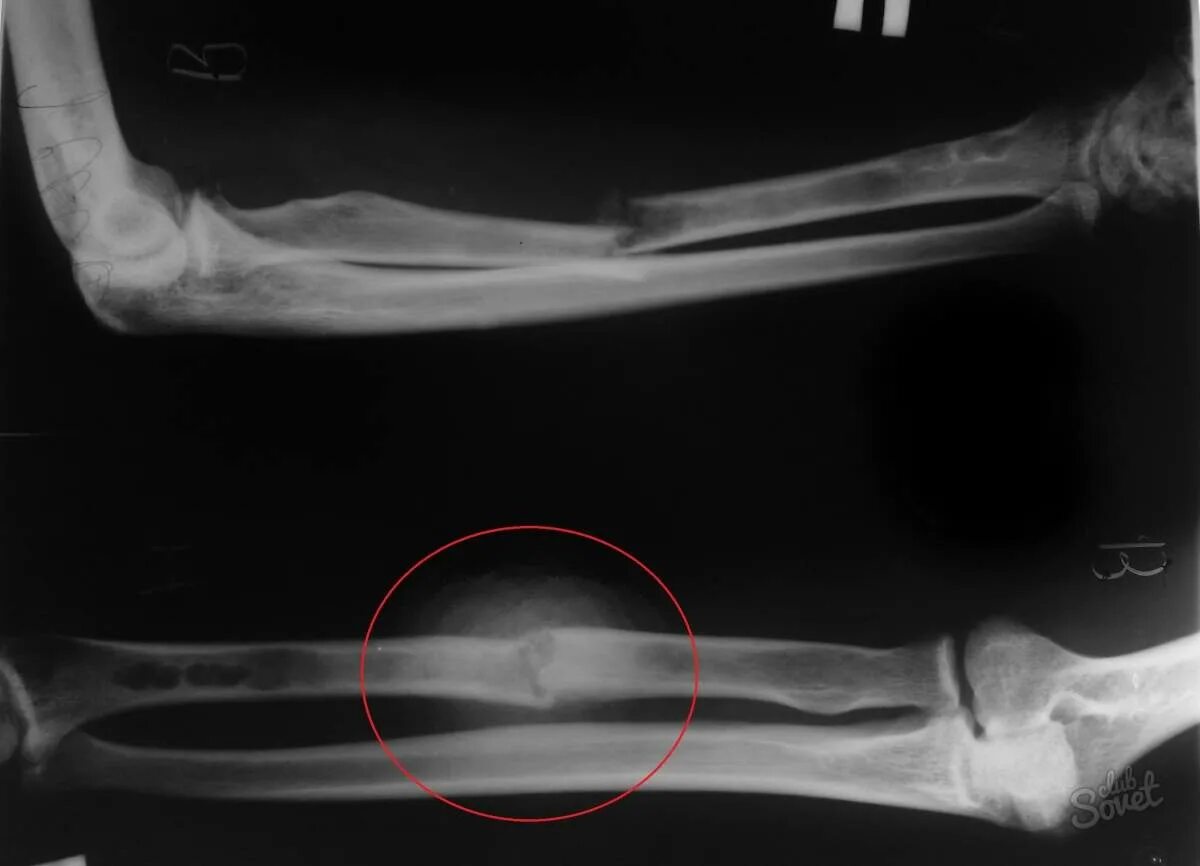

Неправильно срослась кость после перелома